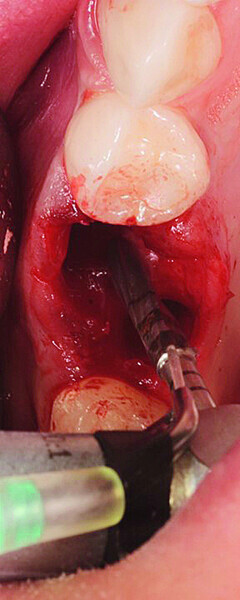

Digital workflow and application of PRF and ozone therapy in oral rehabilitation